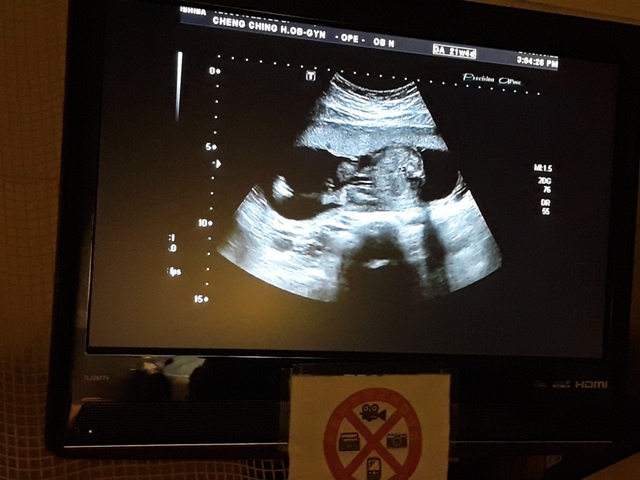

早上和小純去林婦產科看診,今天最主要是要確認有沒有懷孕,過年那段期間,小純跟我說他MC一直都沒來,而且很想吐,用驗孕棒驗的結果,都是懷孕。我第一次去林婦產科,他是一家蠻大間的診所,裡頭有許多孕婦等著看診。

當小純進入診間看診時,我並沒有進去,因為小純說,有時男生不能進去,會被請出來。在外頭等待的我感到很緊張,不久之後,謢理人員請我進入診間,我嚇了一跳,想說發生什麼事了,進入之後,得知小純真的懷孕了,而且已懷了九星期又五天。看診的醫師說,驗孕棒第二條線淡淡的,沒想到胚胎照出來那麼大了,說Baby很健康。還說一閃一閃的是他的心跳,有頭、有手、有腳還有臍帶。小純後來說看了內心覺得很感動,才叫我一起進去看。

小純肚子裡的Baby超音波圖↓